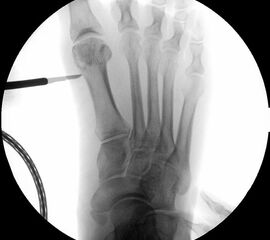

• Korrekturpotential größer als beim offenen Chevron, da die Gelenkkapsel als stabilisierendes Element erhalten bleibt und über eine trikortikale Osteosynthese mit zwei kanülierten Schrauben eine Verschiebung bis ca. 80% des Metatarsaledurchmessers möglich ist (Abb. 1).